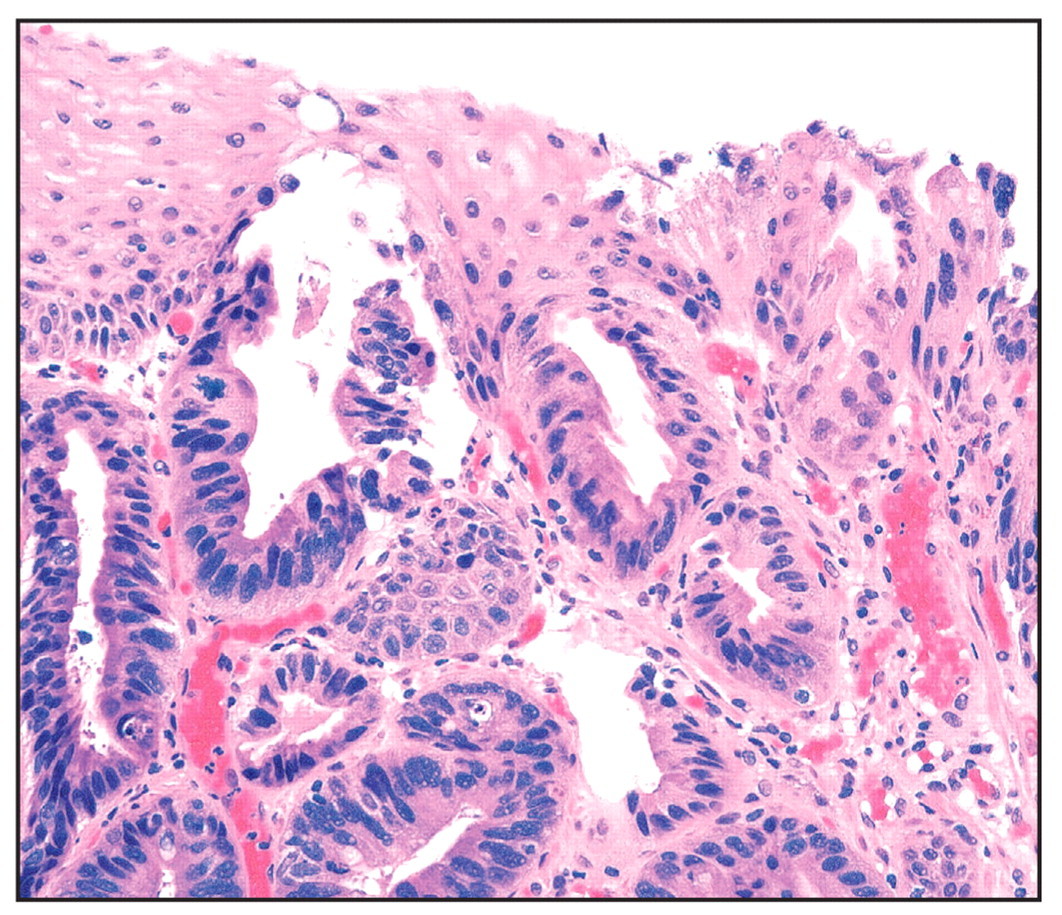

Dx?

GERD

(Notice epithelium is all still squamous; nuclei in desquamated cells; lymphocytes, PMNs, and eosinophils present)

What is this patient’s risk of developing esophageal adenocarcinoma?

~0.5%

(Barrett’s esophagus - notice non-ciliated columnar epithelium with goblet cells next to normal squamous epithelium)

High-grade dysplasia, Barrett’s

(Irregular glands, nuclear atypia)